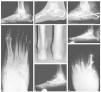

Aproximadamente el 1,5% de los pacientes con diabetes mellitus tiene evidencias radiológicas de neuroartropatía. En EE.UU., donde la población diabética se estima en 16 millones de habitantes, este pequeño porcentaje representa la cifra de 250.000 casos. La artropatía de Charcot se puede también producir en pacientes con mielomeningocele o tras antecedentes traumáticos o quirúrgicos en adultos jóvenes con una alteración motora lumbar baja o sacra alta1. En estos casos, el nivel motor funcional es más bajo que el sensitivo. Además de estas causas frecuentes, la artropatía puede desarrollarse en personas mayores de elevada estatura (fig. 1). La excesiva longitud de los axones de las neuronas en pacientes que miden cerca de los dos metros hace que se degeneren progresivamente y que se pueda producir un pie neuropático a la edad de 60 años.

Figura 1. A: varón de 58 años de edad y 2 metros de altura con niveles normales de glucosa, en la radiografía lateral en carga se aprecia un colapso a nivel de la articulación de Lisfranc y astrágalo escafoidea con hundimiento del arco medial. B: proyección oblicua que muestra la desintegración de la articulación de Lisfranc y posteriores, así como una fractura del quinto metatarsiano. C: radiografía lateral en la que se muestra un enclavamiento intramedular desde la cabeza del primer metatarsiano en la columna medial hasta el cuerpo del astrágalo, y enclavamientos anteriores y posteriores. El tornillo en la parte medial del pie aparece roto, pero el paciente no mostró sintomatología, por lo que no precisó revisión. D: una radiografía oblicua muestra el buen alineamiento y consolidación suficiente.